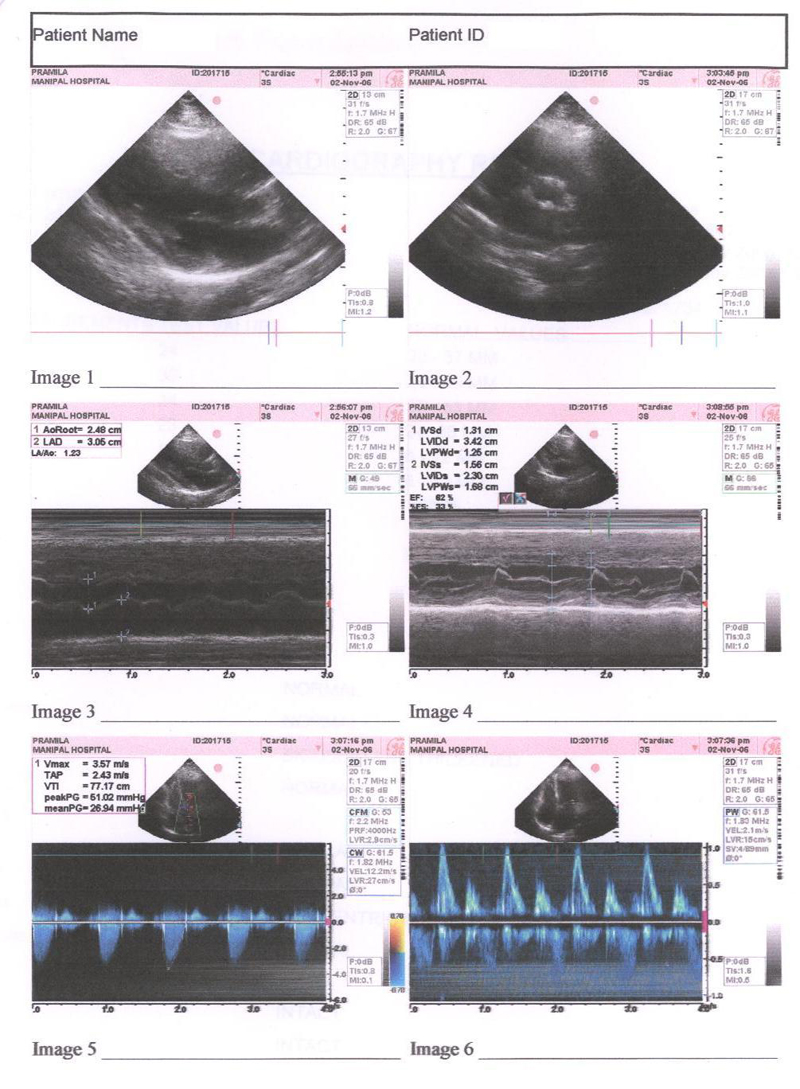

Echocardiography was done indicating a normal heart and patient is un symptomatic. Final Echocardiography was done and shown in FIG 4

FIG 4:- Echocardiography report of 4th JAN 2008